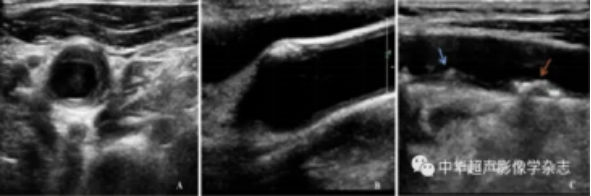

超声报告中“低回声”、“强回声”和“混合回声”是啥意思?这几个词语是超声检查的术语。不能简单理解为低回声就是不稳定斑块;强回声就是稳定斑块;而混合回声就是半稳定斑块。研究表明,回声的高低强弱与动脉硬化斑块的稳定性之间不存在对应的规律。因为颈动脉斑块不同成分对声波的吸收及反射不同,才导致颈动脉斑块超声表现也不尽相同:低回声斑块:含有大量脂类物质的纤维脂肪的斑块;等回声斑块:以胶原蛋白为主要构成成分的纤维斑块;强回声斑块:斑块钙化时,斑块产生强反射伴后壁声影;不均质回声斑块:斑块内有20%以上的回声不一致,斑块内包含强、中、低回声。

不同颈动脉斑块回声灰阶超声图像 A:颈动脉低回声斑块图像;B:颈动脉强回声斑块图像;C:颈动脉混合回声斑块图像,蓝色箭头表示低回声为主混合回声斑块,红色箭头表示高回声为主混合回声斑块。